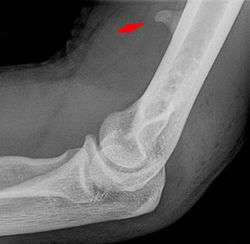

![]() Larger supracondylar process seen on a lateral radiograph of the elbow | |

The supracondylar process of the humerus is a bony projection on the anteromedial aspect of the upper arm bone (humerus), about 5 cm above the medial epicondyle. It is directed downward, forward and medially pointing to the medial epicondyle. It is an anatomical variation which occurs in about one percent of all people. A fibrous band, Struthers ligament, may connect this process to the medial epicondyle.